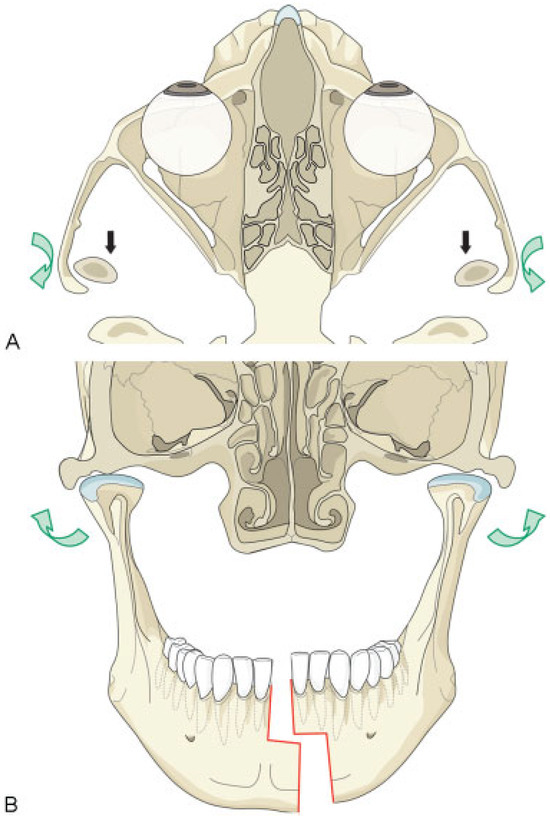

Discussion